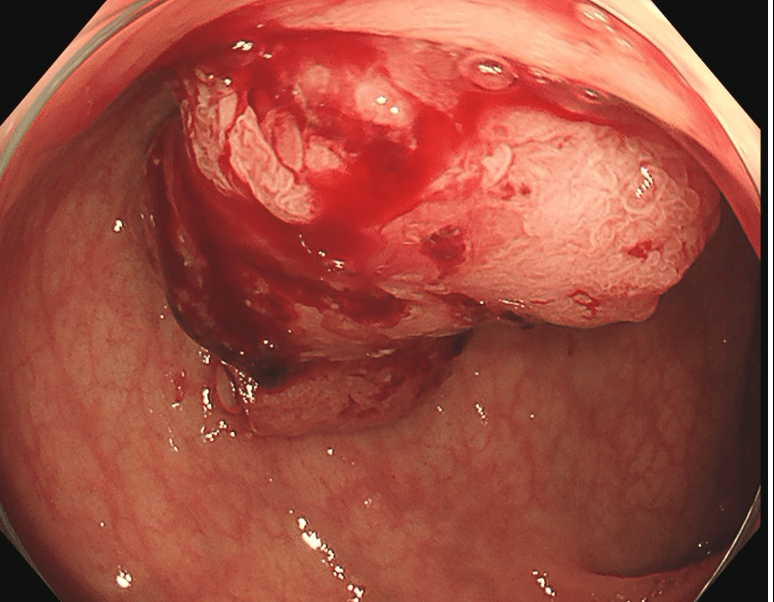

内視鏡的切除

肛門から挿入したスコープ(カメラ)でがんのある部位を切除します。おなかを切ることがないため、術後の痛みがほぼなく、入院期間も短かく済みます。がんが粘膜内にとどまっている場合のみ適応があり、それよりも進行している場合は手術をはじめとした他の治療が行われます。

大腸がんに対してTNT療法を行った例

治療前

治療後